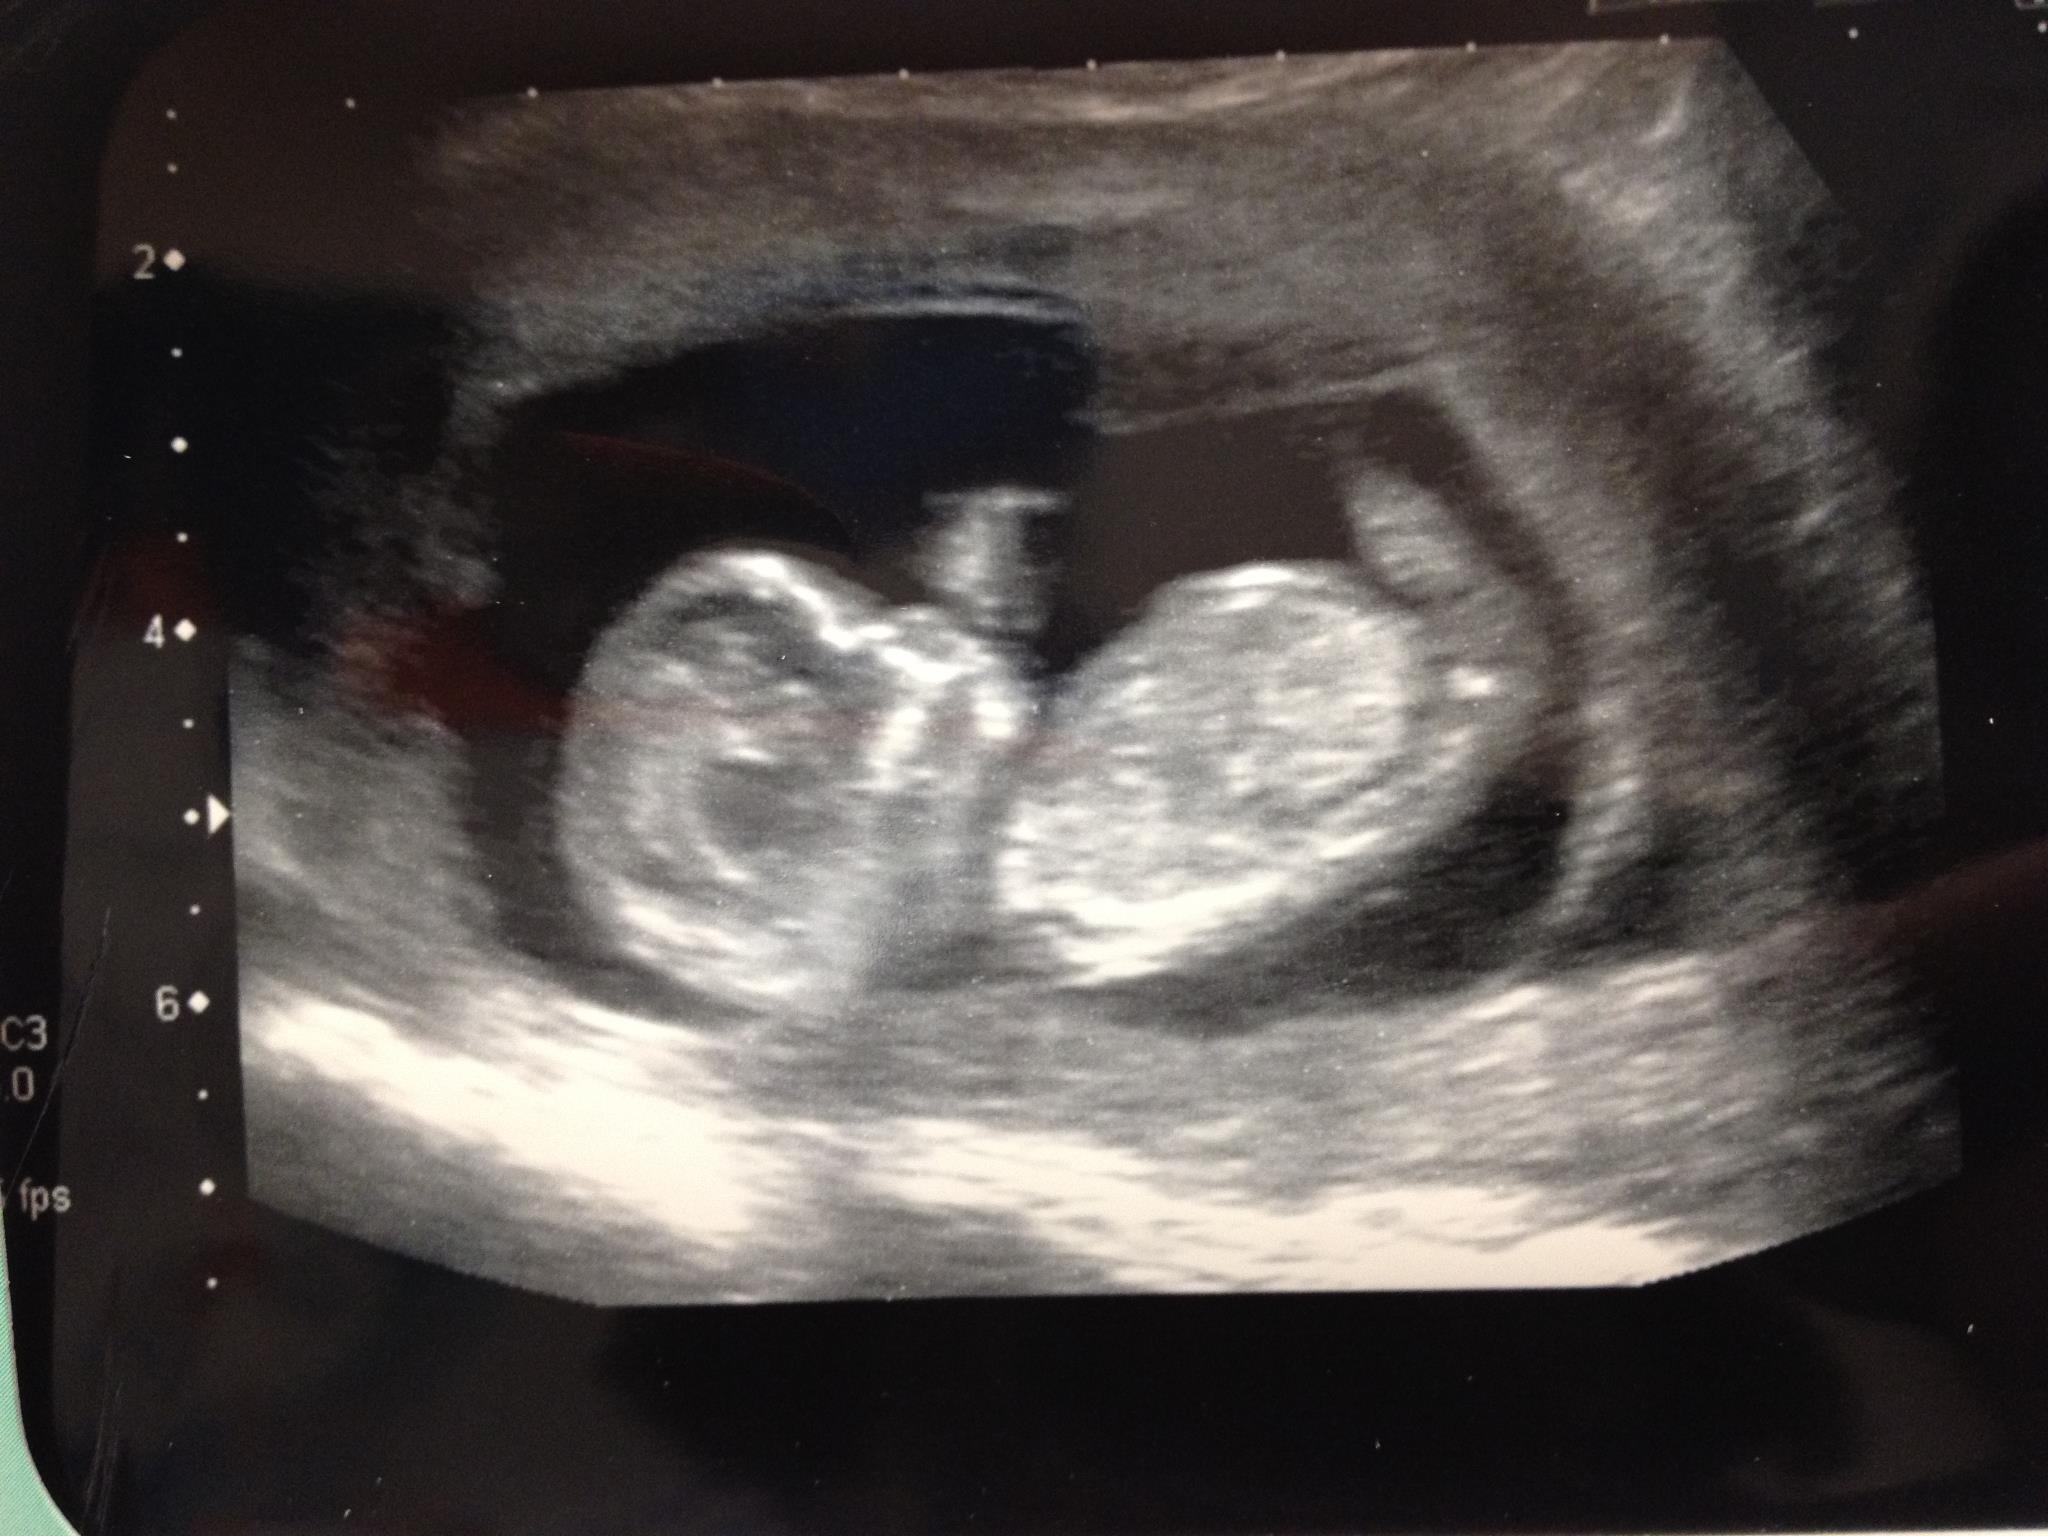

Im pretty sure a nub isnt visible on this scan, but please have a guess on the Skull theory.

This was done at 11+6, although now 16 weeks.